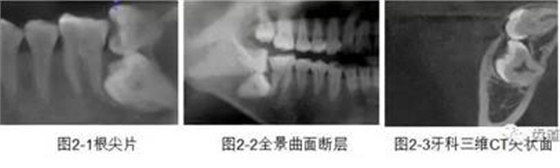

下頜第二第三磨牙阻生口腔曲面斷層片影像

下頜第二第三磨牙阻生CBCT影像定位

三種圖片的影像學比較